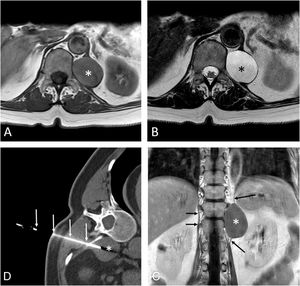

A 58-year-old woman complained of chest discomfort. A computed tomography (CT) identified a low-attenuation retrocrural soft-tissue lesion at the level of T12, suggesting the diagnosis of a nerve sheath tumor or a focus of extramedullary hematopoiesis. Magnetic resonance imaging (MRI) showed a cystic nature, with a differential diagnosis that included a lymphangioma/lymphocele, a cystic nerve sheath tumor, or a chronic hematoma (Fig. 1A–D). A CT-guided fine-needle aspiration (FNA) of the lesion was performed (Fig. 1E), revealing the presence of benign-appearing ciliated columnar epithelial cells within a mucinous background. Based on these findings, a diagnosis of bronchogenic cyst (BC) was made. The patient was referred to thoracic surgery but, given that the cyst had been partially evacuated and that the symptoms had subsided, conservative management was decided.

(A and B) Axial T1-weighted (A) and T2-weighted (B) MR images show a well-defined retroperitoneal lesion (asterisk) involving the left crus of the diaphragm. (C) Coronal T1-weighted MR image following the administration of iv contrast confirms the cystic nature of the mass (lack of enhancement) and better shows the relationship of the lesion with the crus of the left hemidiaphragm (long arrows); note the normal appearance of the right crus of the diaphragm (short arrows). (D) Axial CT image (mediastinal window) shows the fine-needle aspiration procedure (arrows) of the lesion (asterisk).